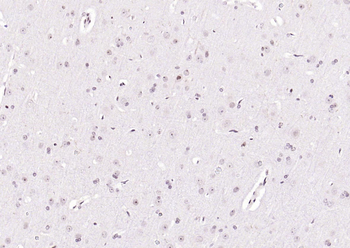

50 μl, 100 μl - KLF4 Recombinant Rabbit Monoclonal Antibody [orb608075]Featured

FC, ICC, IF, IHC-Fr, IHC-P, WB

Human, Mouse, Rat

Rat

Rabbit

Recombinant

Unconjugated

200 μl, 50 μl, 100 μl - Featured